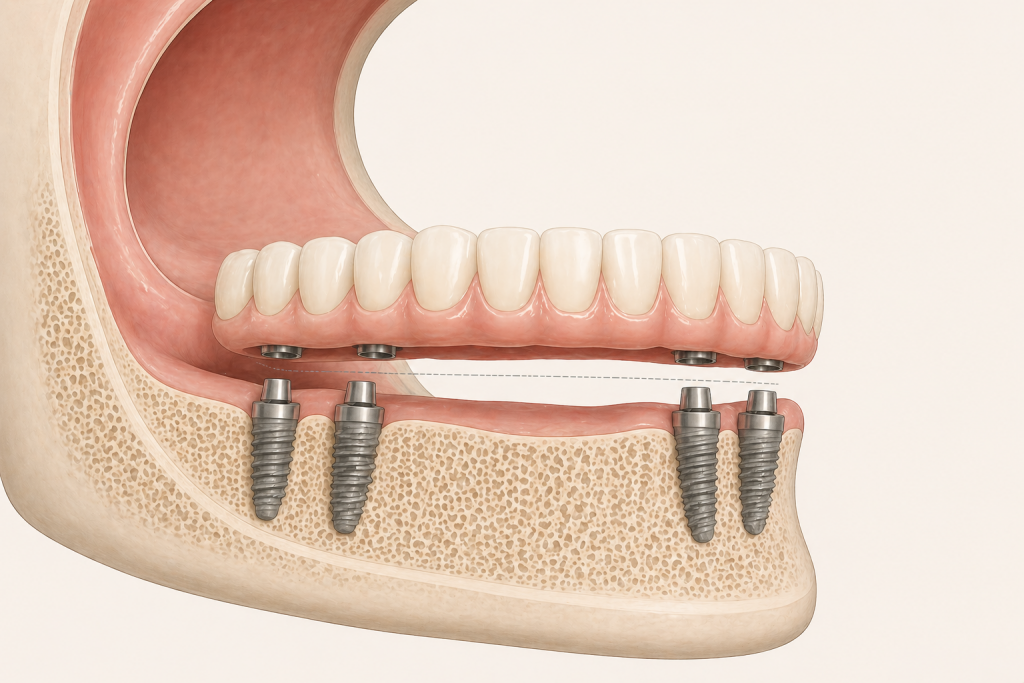

Gli impianti sono strutture in titanio inserite nell’osso che sostituiscono le radici dei denti.

Su questi impianti viene poi costruita una protesi fissa, che non si rimuove e che permette di recuperare funzione ed equilibrio.

Il numero degli impianti non è una scelta commerciale. È una decisione clinica.

In alcune situazioni 4 impianti possono essere sufficienti per sostenere una protesi completa, in altre 6 impianti permettono una distribuzione più ampia dei carichi e una maggiore stabilità nel tempo.

La differenza non riguarda solo “quanti impianti”,

ma come la forza della masticazione viene gestita negli anni.